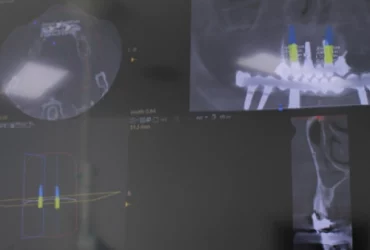

Diagnóstico 3D

Implantología